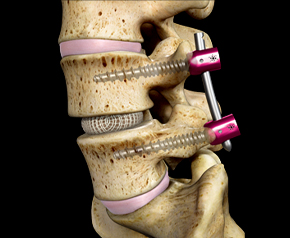

비수술 치료에도 증상이 호전되지 않거나 보행 장애가 심각한 등 일상생활에 지장이 있다면 수술 치료를 시행하하며 양방향척추내시경 및 미세현미경레이져수술,

척추유합술 등을 통해 치료합니 다.